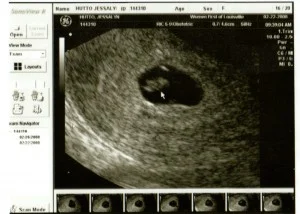

The next day the young wife and her brave husband sat in a dark room next to the glow of a computer monitor showing their baby. Their precious baby, so small, so miraculous.

“It is hard to tell at this point,” the caring voice cautioned, “Usually there is a heart beat, but sometimes not yet.”

Not yet? Could the young wife cling to those words? “Can we have that picture?” she asked hesitantly.

One picture. One piece of evidence. Proof that a baby had existed. One glimpse into their possible future.